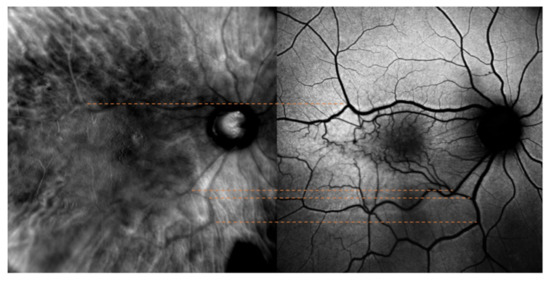

The optic nerve’s superior and inferior margins and retinal blood vessels on color fundus photography (blue lines and orange lines, respectively) were matched with their counterparts identified on retromode images, as shown in Figure 1. On the other hand, while FAF images were matched to retromode images using the retinal blood vessels alone (orange lines Figure 2), for OCT B-scans we used both the neuroretinal rim (grey lines) and the extension of the ERM itself. Particularly, the ERM margins on OCT images were projected onto the retromode image through orange lines, whereas black lines parallel to those originating from the neuroretinal rim were used to project the cystic spaces identified on OCT B-scans to their retromode counterparts (Figure 3).

Figure 1. Retromode and fundus photography correspondence: optic nerve vertical outlines’ poles (blue lines) and retinal vessels (orange lines) are used as reference points to check for appropriate image matching.